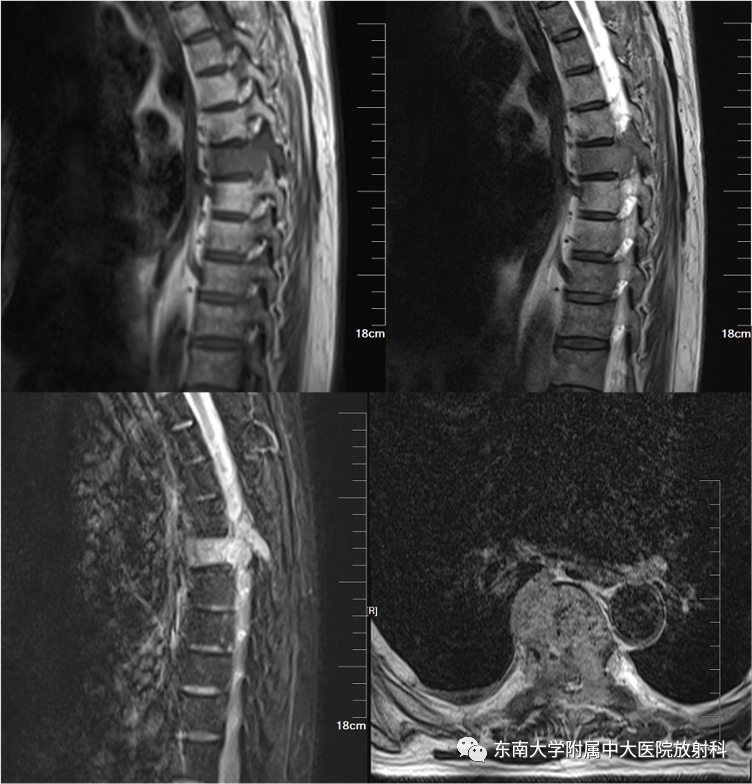

男,51岁

主诉:腰背部疼痛伴行走困难进行性加重10月

辅助检查:免疫球蛋白定量分析正常,尿轻链KAPPA LAMBDA定量:尿KAP:12.9mg/L↑。M蛋白分析:检出κ型IgG单克隆免疫球蛋白抗体